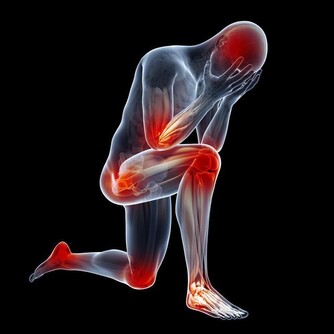

缺鐵性貧血不僅僅是貧血這樣簡單,它能夠導致機體免疫力的下降,降低人們對疾病的抵抗能力。而且,缺血即缺氧,骨骼肌中的呼吸酶、線粒體氧化酶等含量都會下降,致使患者出現乏力、氣喘、活動力下降等表現。

缺鐵貧的患者需要尤為小心心血管事件,貧血是個全身性的疾病,機體處於一個缺氧的狀態,所以全身的各個臟器都會受到影響,只不過,相較於其他的器官,心臟、大腦這些用氧量更多的器官,受到的波及會更大,既往有冠心病、腦梗等患者需要格外小心。